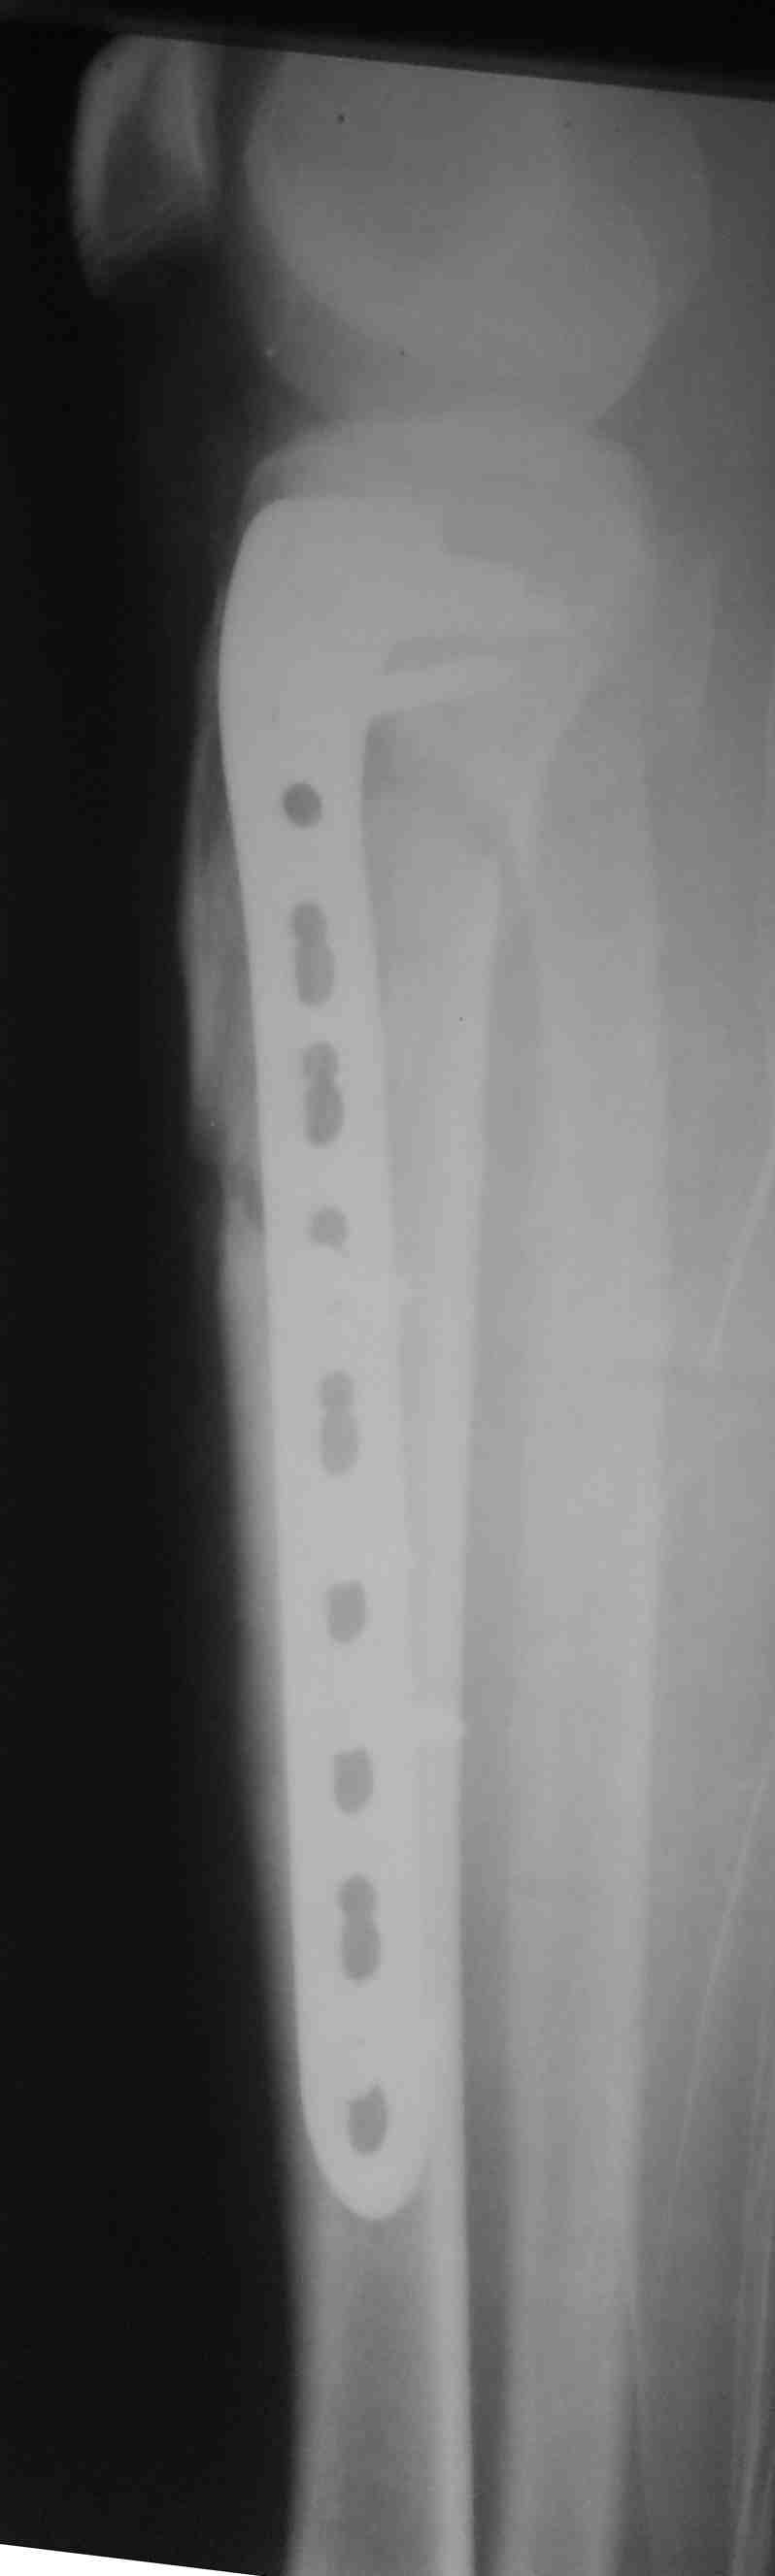

Похожий случай, вчера прооперировали. Непрямая репозиция, малоинвазивный остеосинтез без обнажения зоны перелома.